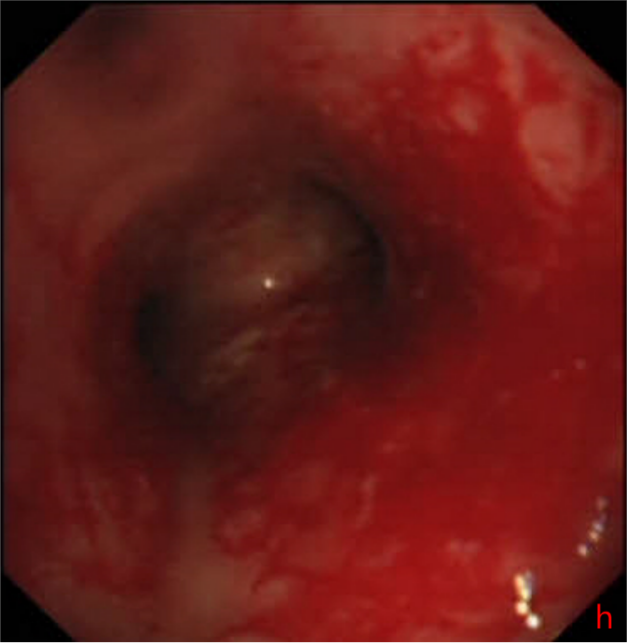

2025年10月10日,手术在全麻下顺利开展。医护团队通过支气管镜的精准引导,将支架成功植入患者气管狭窄部位,整个过程平稳有序。术后奇迹很快显现:W先生的呼吸困难症状当场明显缓解,复查胸片提示气道下段通畅度显著改善,没过多久便能正常进行日常活动。短暂恢复后,他顺利返回继续接受胸部肿瘤放疗,整个放疗过程进展顺利,胸部肿瘤明显缩小。

同年12月19日,W先生再次来到温岭市第一人民医院,在接受肿瘤相关治疗的同时,医护团队为他实施了支架取出手术。术后检查显示,他的气管保持通畅,呼吸顺畅,目前生活状态良好,已恢复正常生活节奏。